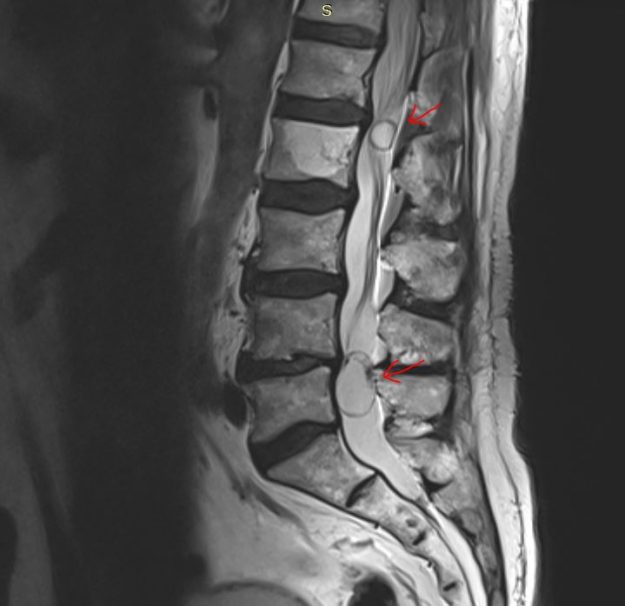

Νεαρή ασθενής 17 ετών με εκτεταμένη συριγγομυελία από την αυχενοπρομηκική συμβολή έως το τελικό τμήμα του νωτιαίου μυελού, λόγω συνδρόμου Chiari. Κλινικά αιμωδίες (μουδιάσματα) άνω άκρων, ζάλη. Αφού ο εργαστηριακός έλεγχος απέκλεισε συνοδά προβλήματα (πχ καθηλωμένο τελικό νημάτιο κ.α.) αποφασίστηκε η επέμβαση αποσυμφόρησης του οπισθίου κρανιακού βόθρου με ανάδυση των αμυγδαλών της παρεγκεφαλίδας και μηνιγγοπλαστική.…